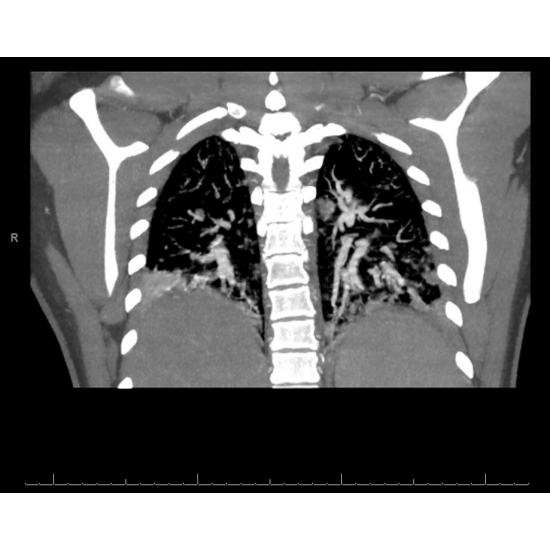

CT Angiogram Pulmonary: Diffuse multifocal consolidations concerning for multifocal pneumonia with mild interstitial pulmonary edema. Case Photo #4 and Case Photo #5